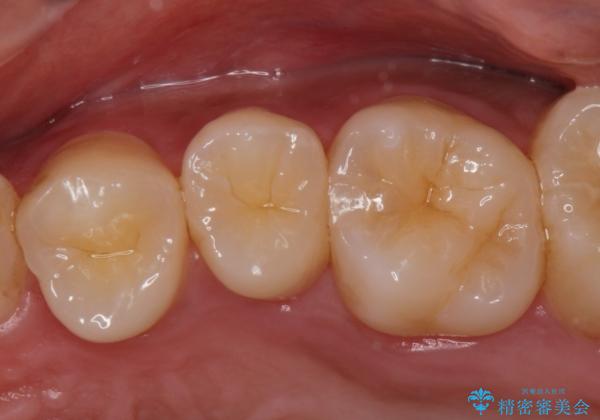

コンタクトカリエス治療。

- 歯と歯の間に虫歯(コンタクトカリエス)が見られたので拡大鏡下で取り除き、e-maxインレーで治療を行いました。

- e-maxインレー 7.7万費用は治療当時の料金となります

歯と歯の間は歯ブラシでは磨けないので毎日フロスや歯間ブラシを使用する事が虫歯になるリスクを下げる事があります。